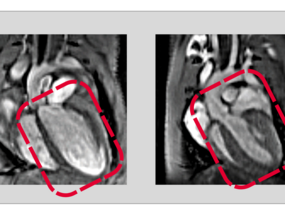

Increasing complexity in the heart: How two related proteins control development of the heart

RBPMS and RBPMS2 regulate cell division and function during heart development